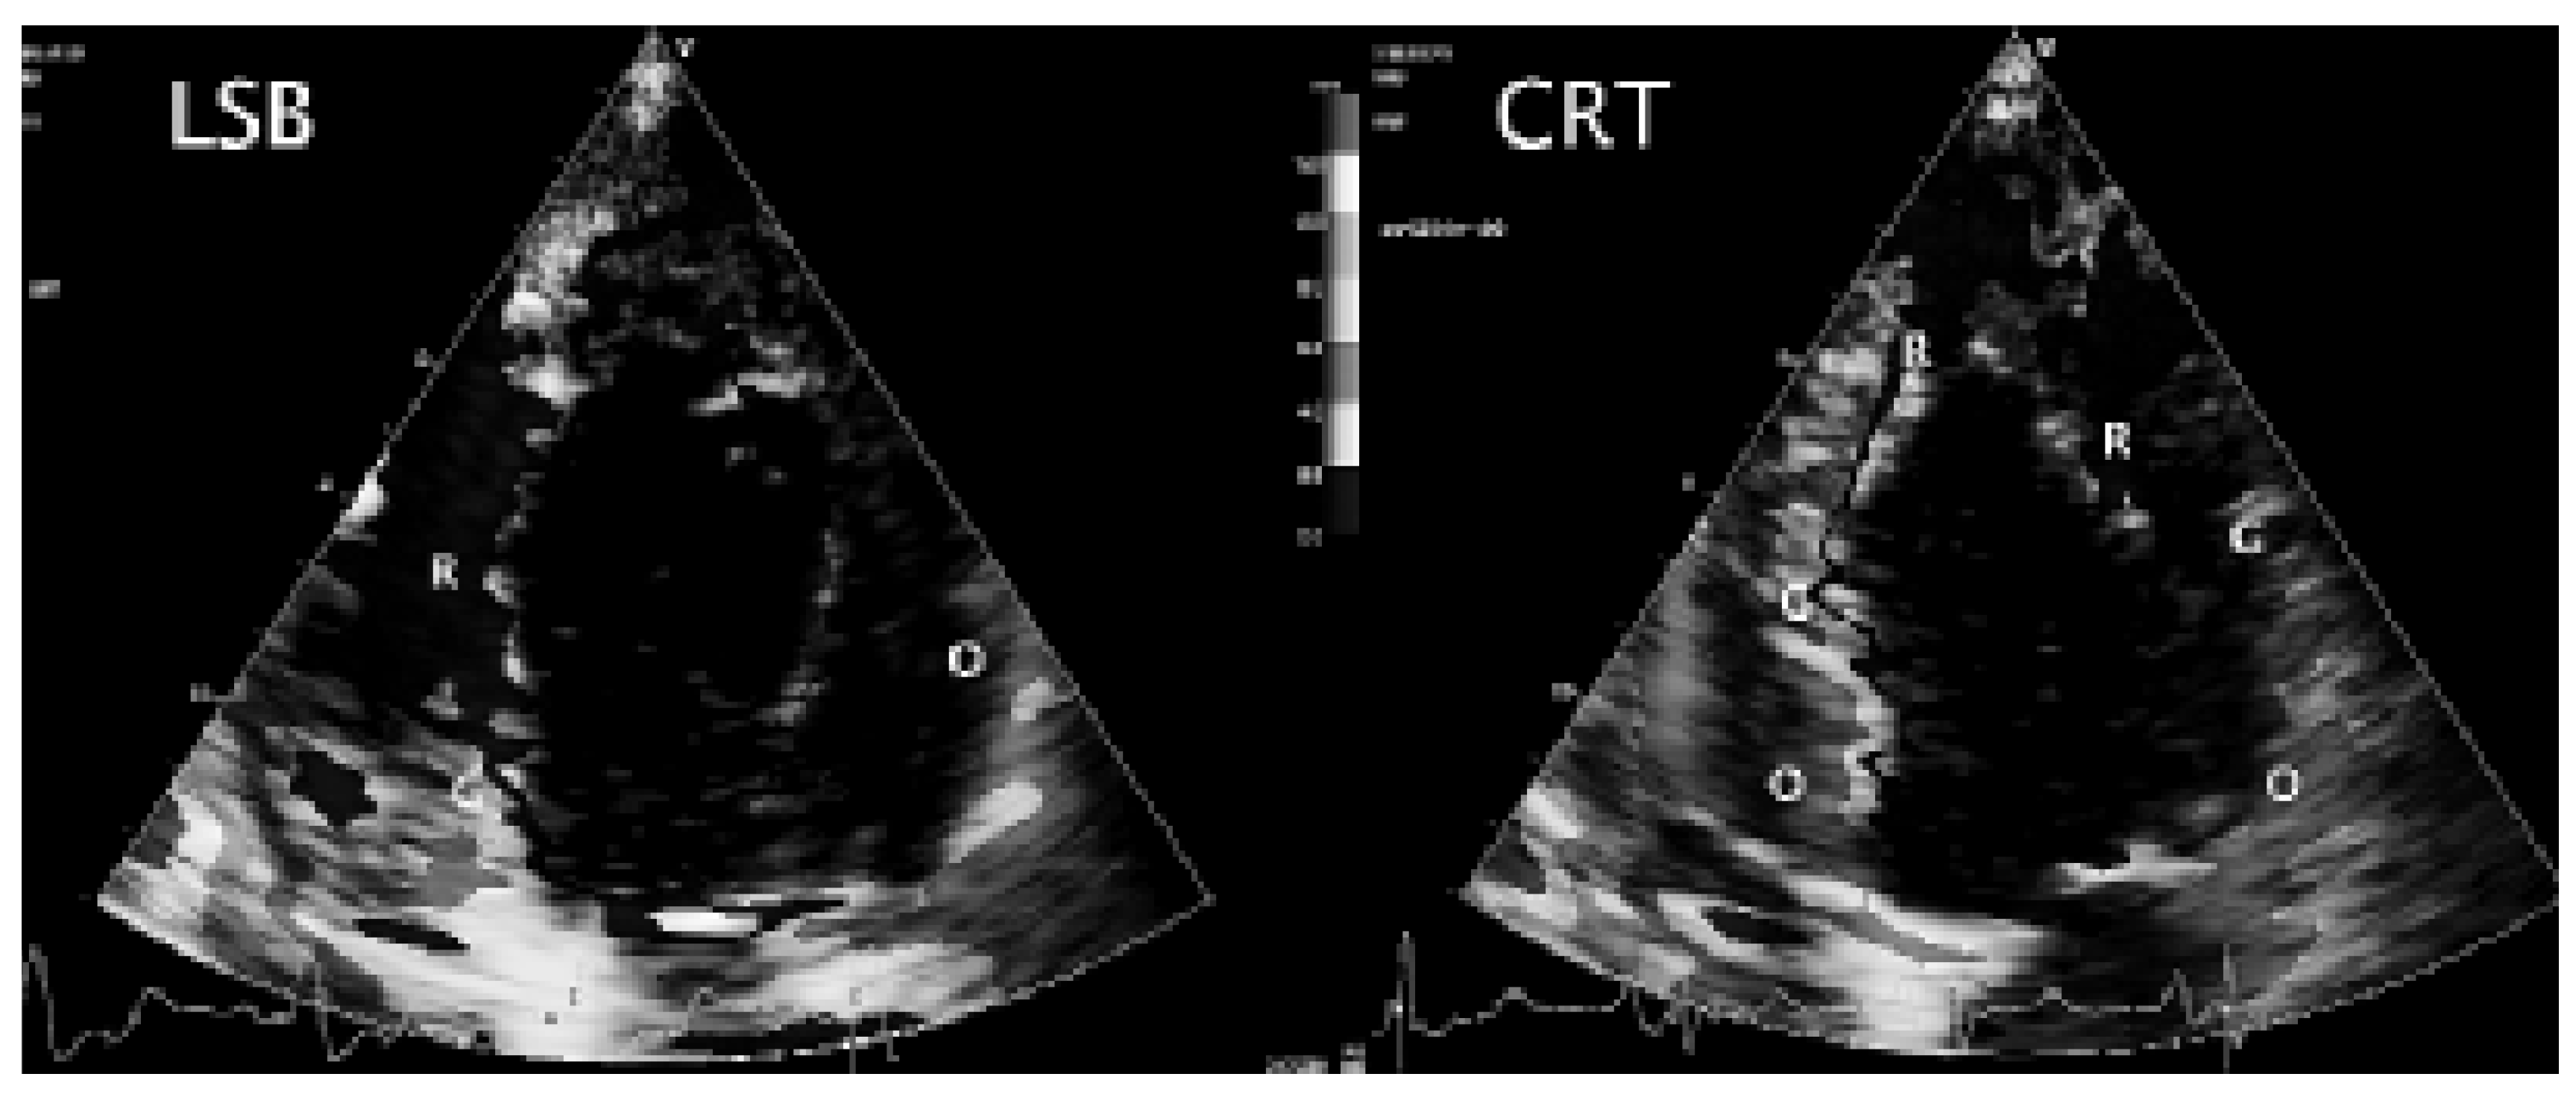

2D- und 3D-Echokardiographie